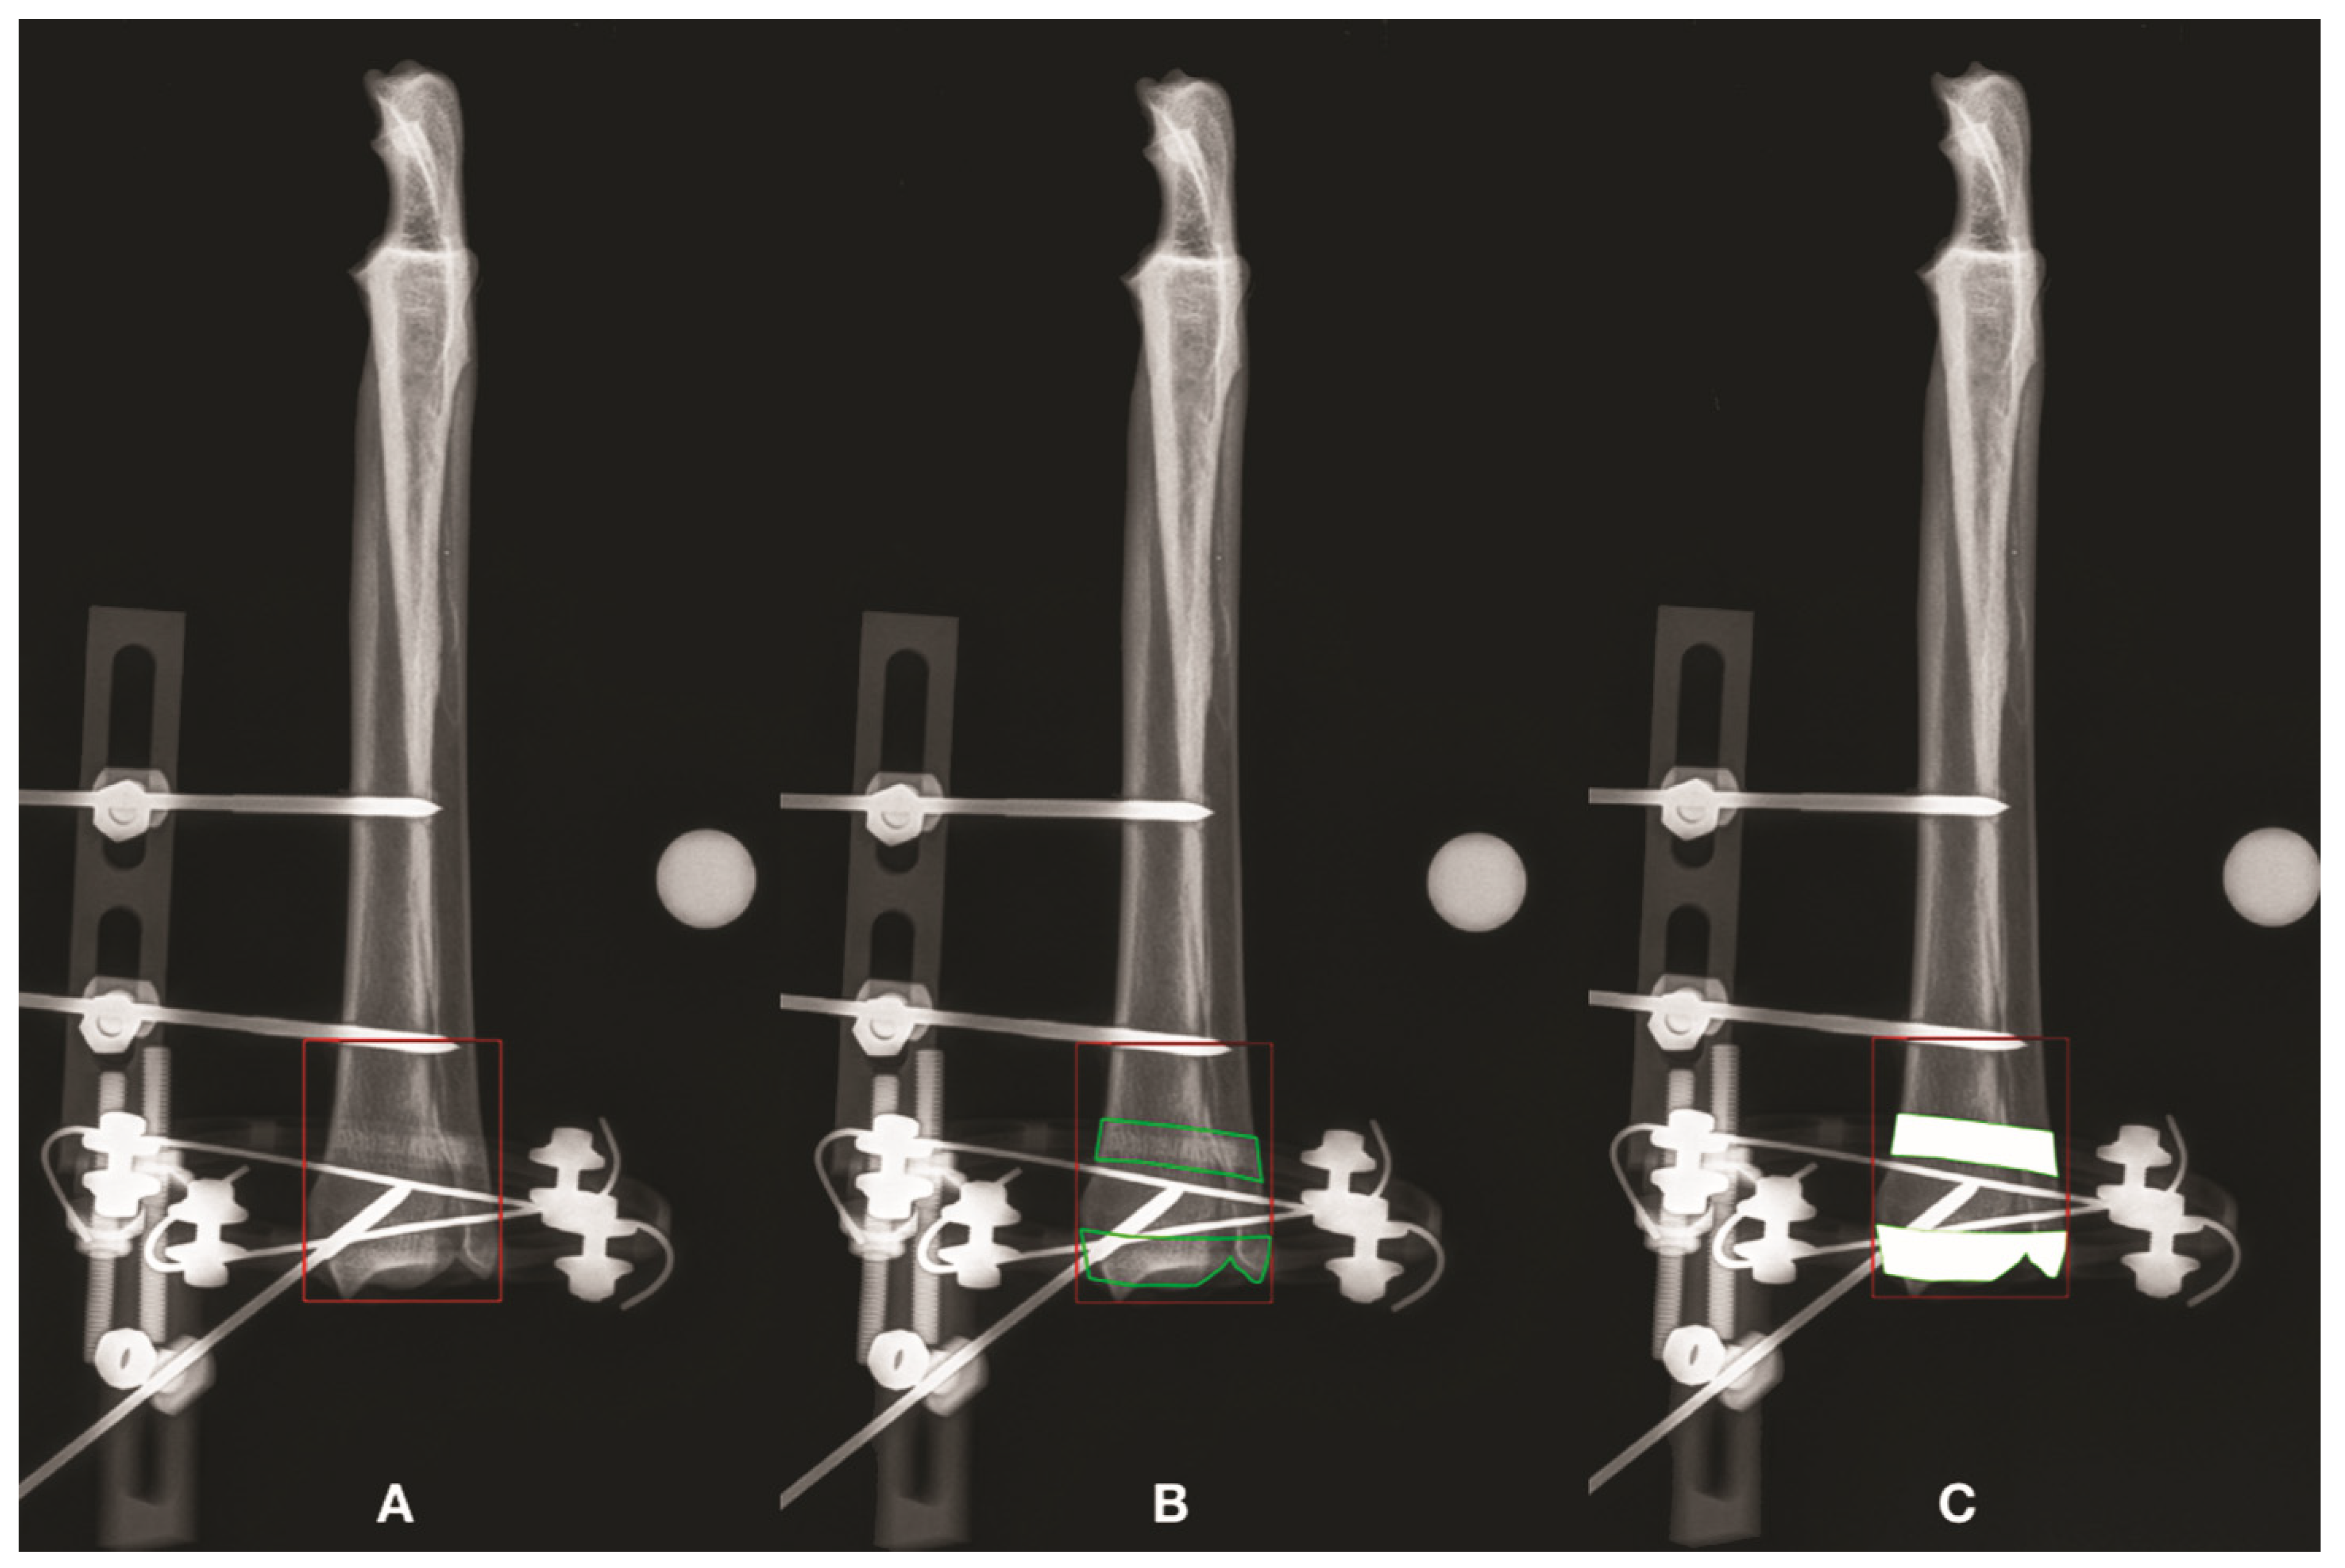

3.3. Tibia

| 1 | AP | 2448.26 | 2448.26 | 2193.1 | 255.16 | 1.00 (100) | 1.12 | 112 | 1.12 | 112 | ||

| 1 | ML | 2368.11 | 1858.46 | 1594.34 | 264.12 | 1.27 (127) | 1.49 | 149 | 1.17 | 117 | ||

| 2 | AP | 2181.06 | 2181.06 | 1906.42 | 274.64 | 1.00 (100) | 1.14 | 114 | 1.14 | 114 | ||

| 2 | ML | 2522.34 | 2118.95 | 1532.54 | 586.41 | 1.19 (119) | 1.65 | 165 | 1.38 | 138 | ||

| 3 | AP | 2034.36 | 2034.36 | 1771.65 | 262.71 | 1.00 (100) | 1.15 | 115 | 1.15 | 115 | ||

| 3 | ML | 1885.76 | 1448 | 1090.29 | 357.72 | 1.30 (130) | 1.73 | 173 | 1.33 | 133 | ||

| 4 | AP | 1994.06 | 1994.06 | 1718.91 | 275.15 | 1.00 (100) | 1.16 | 116 | 1.16 | 116 | ||

| 4 | ML | 1917.27 | 1636.64 | 1241.88 | 394.76 | 1.17 (117) | 1.54 | 154 | 1.32 | 132 | ||

| 5 | AP | 2298.43 | 2298.43 | 1982.56 | 315.87 | 1.00 (100) | 1.16 | 116 | 1.16 | 116 | ||

| 5 | ML | 2171.56 | 1898.04 | 1512.37 | 385.67 | 1.14 (114) | 1.44 | 144 | 1.26 | 126 | ||

| 6 | AP | 2913.71 | 2913.71 | 2614.23 | 299.48 | 1.00 (100) | 1.11 | 111 | 1.11 | 111 | ||

| 6 | ML | 2553.02 | 2283.24 | 1722.48 | 560.76 | 1.12 (112) | 1.48 | 148 | 1.33 | 133 | ||

| Median | AP | 2239.75 | 2239.75 | 1944.49 | 274.89 | 1 | 1.15 | 114.62 | 1.15 | 114.62 | p = 0.0143 | |

| ML | 2269.84 | 1878.25 | 1522.45 | 390.21 | 1.18 | 1.51 | 151.46 | 1.32 | 132.17 | p = 0.0143 | ||

| (range) | AP | (1994.06–2913.71) | (1994.06–2913.71) | (1718.91–2614.23) | (255.16–315.87) | (1.00–1.00) | (1.11–1.16) | (111.46–116.01) | (1.11–1.16) | (111.46–116.01) | ||

| ML | (1885.76–2553.02) | (1448.00–2283.24) | (1090.29–1722.48) | (264.12–586.41) | (1.12–1.30) | (1.44–1.73) | (143.59–172.96) | (1.17–1.38) | (116.57–138.26) |